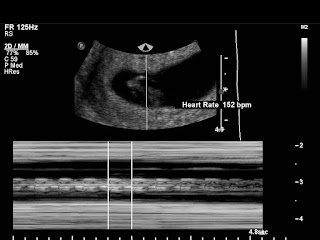

- I have my MFM appt on Tuesday. Pray that everything looks good with baby and that everything looks good to go ahead with surgery.

- And then the obvious, prayers for surgery itself. Pray that there is no unexpected metastases and that the tumor is not invading my vocal nerves too bad (it looked like it might be on the ultrasound), and the Dr.is able to remove it with no complications.